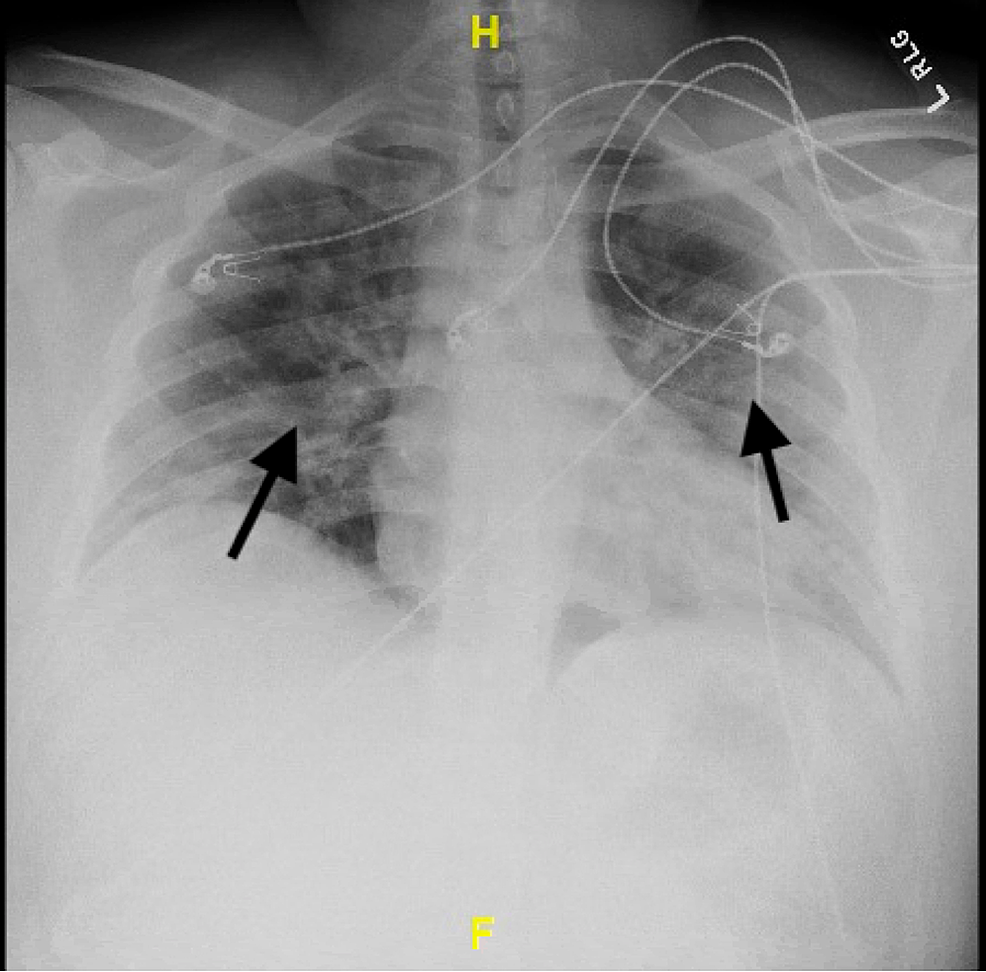

Chest Xray findings at admission. The chest Xray shows a large Chest X Ray Findings Myocardial Infarction This test can show how blood moves through the heart and heart valves. Features of myocardial infarction (e.g., chest pain, nausea, vomiting). Respiratory distress, pallor, diaphoresis, tachycardia, high/low bp, s4 heart sound, signs of mitral regurgitation, pulmonary oedema. Chest radiography is useful in determining the presence of cardiomegaly, pulmonary edema, pleural effusions, kerley b lines, and other criteria of hf.. Chest X Ray Findings Myocardial Infarction.

Chest X Ray Findings Myocardial Infarction Chest radiography is useful in determining the presence of cardiomegaly, pulmonary edema, pleural effusions, kerley b lines, and other criteria of hf. Sound waves (ultrasound) create images of the moving heart. Features of myocardial infarction (e.g., chest pain, nausea, vomiting). Chest radiography is useful in determining the presence of cardiomegaly, pulmonary edema, pleural effusions, kerley b lines, and other criteria of hf. Respiratory distress, pallor, diaphoresis, tachycardia, high/low bp, s4 heart sound, signs of mitral regurgitation, pulmonary oedema. This test can show how blood moves through the heart and heart valves. Patients may develop severe hypotension following nitroglycerine or morphine. Reduced air entry, coarse crackles) to screen for. The traditional triad of findings seen in rvmi is hypotension, clear lung fields, and jugular venous distention. An echocardiogram can help identify whether an area of your heart has been damaged.